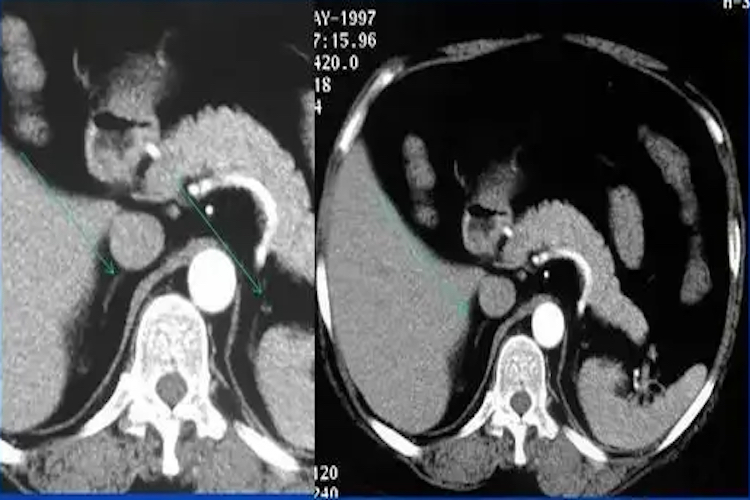

肾上腺肿块:双侧肾性肿块常见于肾上腺转移瘤,但也见于肾上腺结核、皮质腺瘤和嗜铬细胞瘤等。通常良性功能性肿瘤常较小,例如原发性醛固酮增多症和库欣综合征中的腺瘤,直径常分别小于2cm和3cm。肾上腺非功能性肿瘤和恶性肿瘤通常较大,例如肾上腺皮质癌发现时直径多大于6cm。肿块密度均匀水样低密度肿块,呈均一强化常为功能性腺瘤和非功能腺瘤。